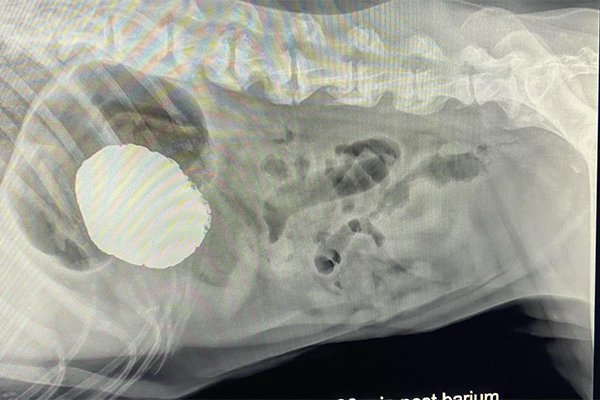

Barium Series

This procedure is a Contrast Study which means that we use a contrast dye that shows up on x-ray and highlights certain structures. Because some objects don’t show up on xray (plastic, fabric, toys, etc), this can help outline it or show us where the obstruction is as it can’t get past.

Our talented Registered Veterinary Technicians administer barium (the contrast liquid) in the mouth and then we take successive X-rays over the next few hours to watch its progress. The first X-ray is almost immediate to catch the outline of the esophagus while the last one may be hours later as it enters the colon .

Flip through the photos to see the progression of barium through the gastrointestinal tract: